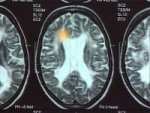

- Autoimmunerkrankung Multiple Sklerose

- Bei Autoimmunerkrankungen wie der Multiplen Sklerose richtet sich die Immunabwehr gegen eigenes Gewebe.

Bei der Multiplen Sklerose werden Nervenbahnen im Gehirn angegriffen. Beim entzündliche Rheuma wird Knochengewebe zerstört.